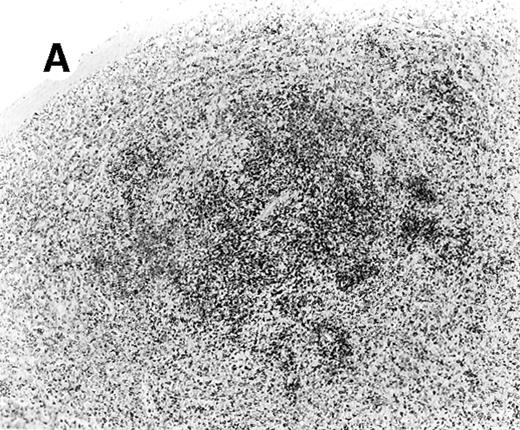

All cases showed essentially similar histologic findings in the liver and spleen. The splenic white pulp was inconspicuous to markedly depleted, whereas the sinusoids showed a prominent lymphoid infiltration (Figure 1A). There was striking hemophagocytosis within the splenic sinusoids (Figure 1B). The infiltrating lymphocytes were small and lacked significant cytologic atypia (Figure 1B). Immunoblasts and plasma cells were not prominent. The liver had prominent portal as well as sinusoidal infiltrates of small lymphocytes morphologically identical to those noted in the spleen (Figure 2). There was intracellular and intracanalicular cholestasis, steatosis, and focal necrosis. Hemophagocytosis was present within the sinusoids. In case 5, the spleen showed extensive areas of necrosis mainly in the perifollicular and periarteriolar lymphoid sheaths of the white pulp with the presence of immunoblasts reminiscent of IM.

Histologic findings in spleen.

(A) Section of spleen from case 2 shows depletion of white pulp and prominent sinusoidal small lymphoid infiltrates (hematoxylin and eosin, × 200). (B) The lymphocytes lack significant cytologic atypia. There is marked hemophagocytosis (hematoxylin and eosin, × 600).